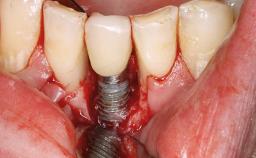

Peripheral Giant-cell Granuloma Associated with Peri-implant Tissues